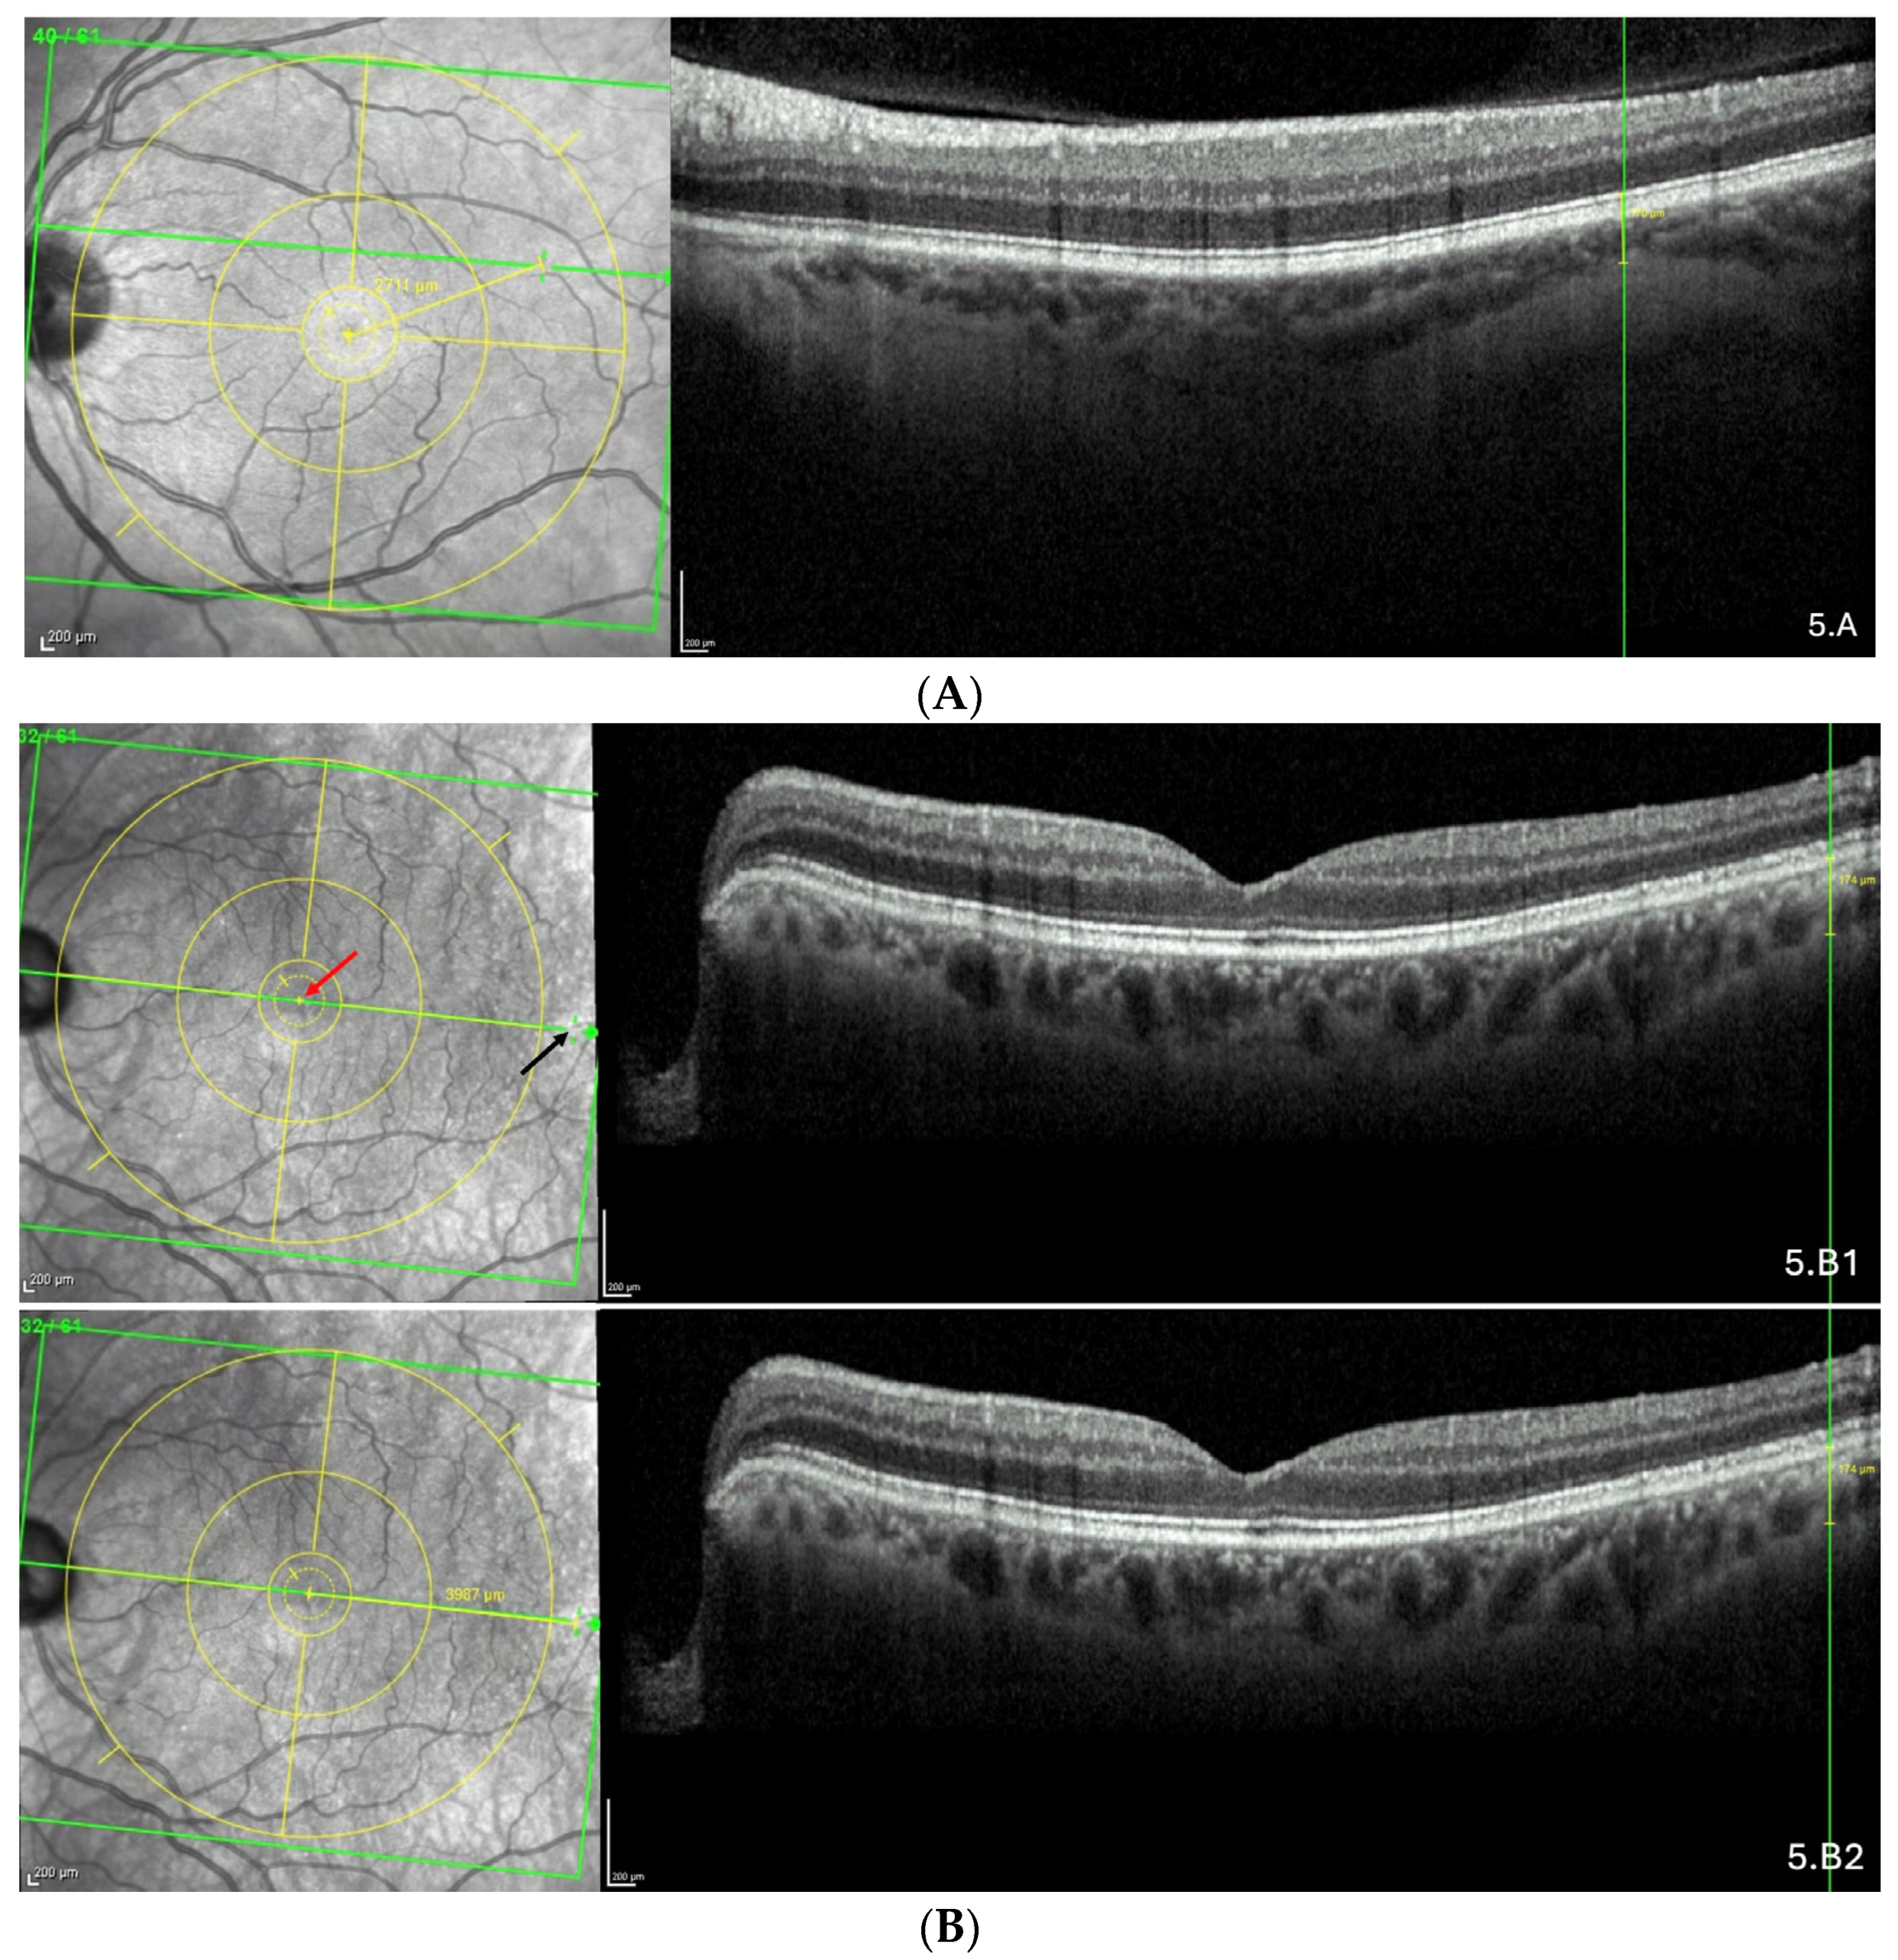

The representative OCT scans of FT-distance in different locations and the corresponding AL and FT-distance values are presented in Figure 5A–C.

Figure 5.

(A) Thinning above the FoBMO axis. Thickness of the thinning: 170 µm. Fovea-thinning distance: 2711 µm. Axial length: 22.04 mm. (B) Thinning along the FoBMO axis; 5B1. Marks of the fovea (red arrow) and the thinning (black arrow) in the IR image; 5B2. Fovea-thinning distance measured between these marks. Thickness of the thinning: 174 µm. Fovea-thinning distance: 3987 µm. Axial length: 23.94 mm. (C) Thinning below the FoBMO axis. Thickness of the thinning: 18 µm. Fovea-thinning distance: 4236 µm. Axial length: 29.86 mm. The yellow box is presented in (C). The red curve underlines the posterior choroidal wall. The green horizontal lines in the infrared images locate the OCT sections. (A–C) The vertical green lines in the OCT sections locate the thinnings which appears as a discontinuity within the horizontal green line of each corresponding infrared image. Abbreviation: FoBMO = Fovea-Bruch’s membrane Opening.